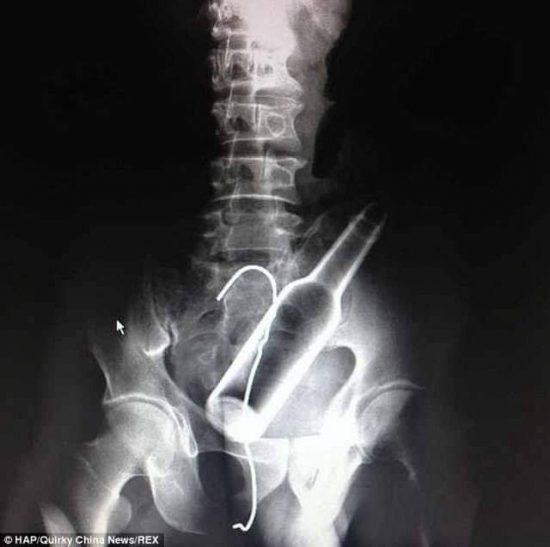

Luego de unos estudios de Rayos X, pudieron observar claramente la ubicación de la botella de vidrio, la cual se localizaba entre el recto y el sismoide, por lo que fue necesario la intervención quirúrgica para extraer el cuerpo “extraño” que reconoció también su poseedor.

Se trato de un procedimiento quirúrgico ambulatorio que duró cerca de 30 minutos, en el cual se buscó relajar el músculo en forma de anillo que abre y cierra la abertura del ano y con unas pinzas extrajeron el cuerpo extraño.